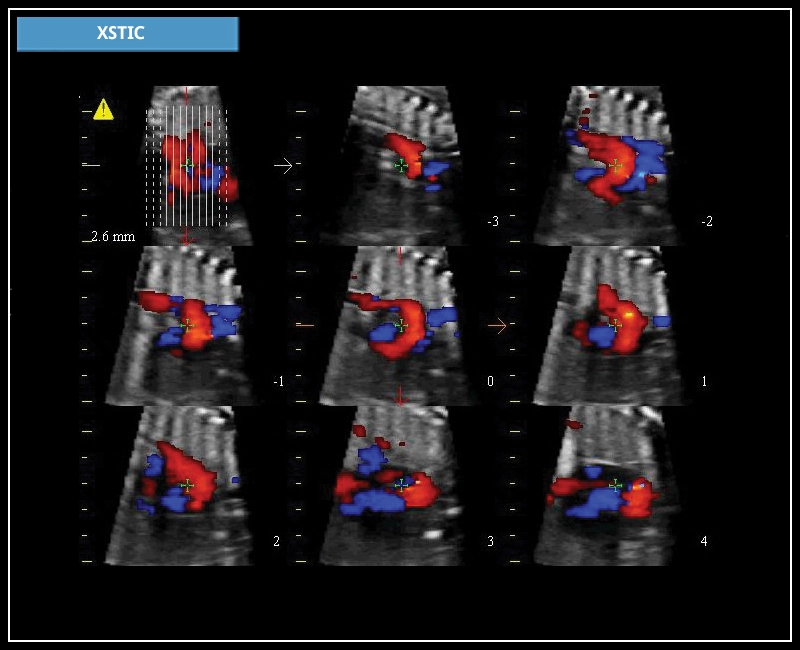

MyLab™X7 - XSTIC

MyLab™X7 - XSTIC